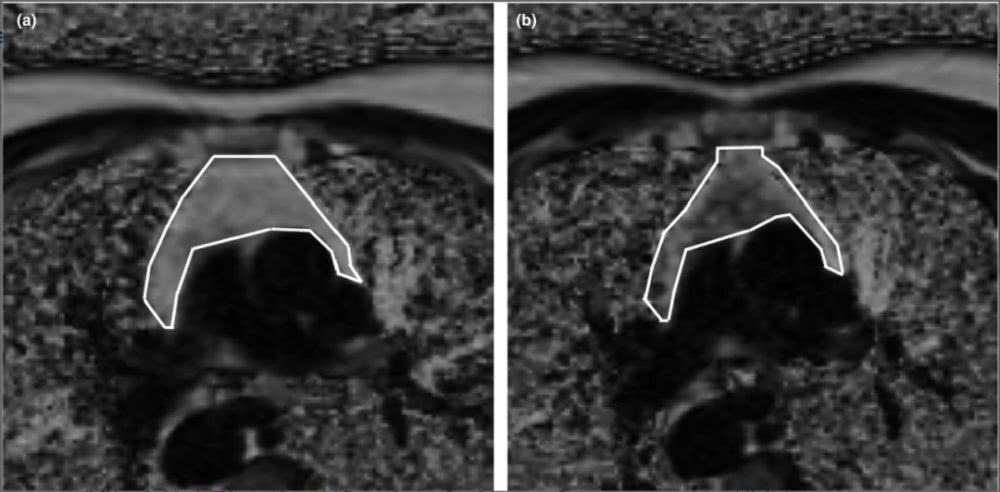

研究人员还在研究开始和结束时使用磁共振成像(MRI)确定胸腺的组成。他们发现,在 7 名参与者中,堆积的脂肪已经被再生的胸腺组织所替代。

▲白线表示胸腺边界,变暗对应于非脂肪组织代替脂肪